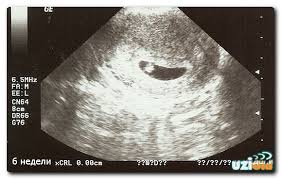

Я в 5 недель акушерских делала, только плодное яйцо увидели, а в 7 уже сердечко билось)

Мне кажется, самый оптимальный вариант - это в 7 недель)

Согласна, лучше потерпеть немножко чтоб вернуться с узи с первой фотографией ляльки